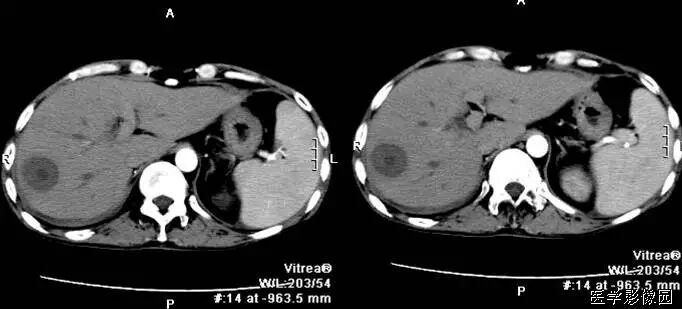

1、靶征(肠套叠)

是肠套叠最常见的特征性CT征像,为肠套叠长轴与CT扫描层面垂直时的表现,反映了套叠的各层肠壁、肠腔及肠系膜间的关系。典型排列为自外向内分别代表鞘部外层肠壁、鞘部肠腔内造影剂、鞘部内层肠壁、偏心性套入部肠系膜、套入部肠壁、套入部肠腔内造影剂。

肠套叠指:一段肠管及与其相连的肠系膜(套入部)被套如其相连的一段长管内(鞘部),导致肠内容物通过阻碍。婴儿由于大肠与小肠管径之比例相差大。故小肠易陷入大肠而被套牢。少数肠套叠可能来自某些器质性病变如美凯尔憩室、肠息肉、异位胰腺小结、血管瘤、异物、复制肠管、淋巴增生、肿瘤、寄生虫等,其中以美凯尔憩室最多,过敏性紫斑也常会合并肠套叠,大于2岁的小孩发生肠套叠,一定要考虑到这些病变。大于5岁的病例中,则以淋巴瘤为最多;成人肠套叠小肠多见,常伴发良性病变;结肠型肠套叠则更多由恶性病变继发。良性病变有脂肪瘤、平滑肌瘤、血管瘤、神经纤维瘤、腺瘤样息肉、美克尔憩室、术后粘连机场动力性病变等;恶性病变有转移瘤、腺癌、类癌、淋巴瘤及平滑肌肉瘤等。由于肠套叠长轴与CT扫描层面的角度不同,表现各异。

如扫描层面和迂曲的肠道相平行时,表现为彗星尾征或肾形征:即套叠近端肠系膜血管牵拉聚拢的征象。一般情况下,慧星尾征均与肾型肿块相伴出现。该肾形肿块为套鞘部游离缘与套入部近端肠管及肠系膜的CT斜切面图像,其中游离的套鞘呈弧形围绕套入部,形状若肾轮廓外形,而套入部近端肠管、肠系膜形状若肾蒂。此时,所谓慧星尾征的组成还应包括套入近端肠管。如果套叠的肠管与CT扫描垂直,则呈靶形征,即肿块影表现为圆形或类似环形。通常在肿块内可分辨出层样结构,推测可能是继发于套入部和鞘部间的液体或是肠壁水肿造成密度对比,类似同心圆形;当套入部肠壁显著水肿坏死或套入部肿瘤周围浸润累及肠系膜,肠系膜血管及脂肪、套叠时间较长,套入部系膜血管受挤压时,静脉血液回流障碍,套入部肠壁充血水肿、变硬,形成不完全性肠梗阻,套叠以上肠管蠕动增强,可引起代偿性肠管扩张肥厚,并可见肠系膜连同其血管纠集、扭曲,形成“漩涡征”。